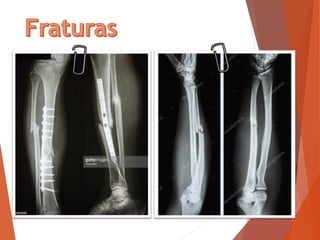

Fratura fechada (interna)

 Quando não há o rompimento da pele

 Sintomas:

 Incapacidade de movimentar.

 Dor intensa;

 Deformação;

 O que fazer:

 Sempre que possível, chame e espere o socorro

especializado;

 Se for necessário conduzir a vítima ao hospital imobilize

os locais afetados fazendo “talas”

movimente a vítima antes de imobilizar os

locais afetados

Fratura aberta (exposta)

 Quando há o rompimento da pele

 Não tente colocar o osso no lugar

 Cubra com um pano limpo

 Lave com água corrente ou soro fisiológico

 Se houver sangramento intenso faça compressão no local